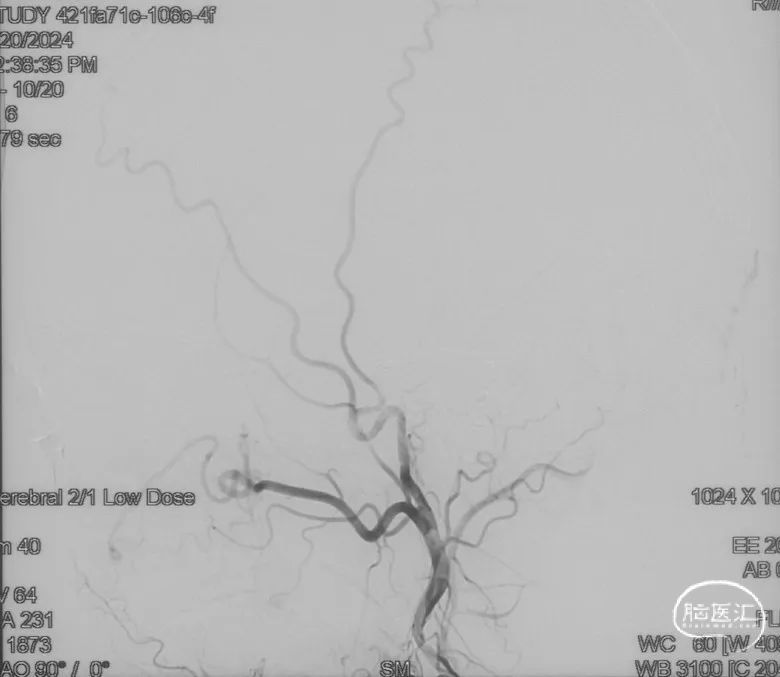

术前造影

证实为TDAVF,为岩上窦型。R-ECA正侧位见右侧脑膜中动脉分支、枕动脉分支、颞浅动脉分支向瘘口供血,经幕上迂曲扩张的静脉、中脑周围静脉、基底静脉向深部静脉引流。

选取工作角度,正侧位造影

Echelon-10微导管在ASAHI 0.010微导丝导引下经右侧脑膜中动脉分支超选至瘘口,可见瘘口口径大,微导管直接越过瘘口,进入引流静脉起始部。

Marathon微导管在ASAHI 0.010微导丝导引下经右侧脑膜中动脉分支超选至瘘口近端。

经Marathon微导管手推造影明确微导管位于瘘口动脉端,Echelon-10微导管位于瘘口引流静脉起始端处扩张的静脉球内。